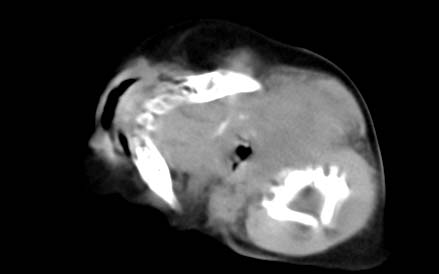

男,26天,发现左侧颈部包块5天,质较硬,患儿不哭不吵,无明显发热,头向右侧歪斜,其父母诉患儿出生时正常,昨天查血象wbc19.4×10的9次方/l,b超考虑来源于甲状腺的恶性肿瘤,我科认为肿块内有低密度区,而且病程发展较快,血象高,考虑炎性病变可能大。患儿年龄太小没做增强。请大家提出高见。

男,26天,发现左侧颈部包块5天,质较硬,患儿不哭不吵,无明显发热,头向右侧歪斜,其父母诉患儿出生时正常,昨天查血象wbc19.4×10的9次方/l,b超考虑来源于甲状腺的恶性肿瘤,我科认为肿块内有低密度区,而且病程发展较快,应该首先排除血肿,其次考虑感染

随访结果:炎症(患儿经过一星期抗炎治疗后颈部包块明显缩小,现已经正常)。